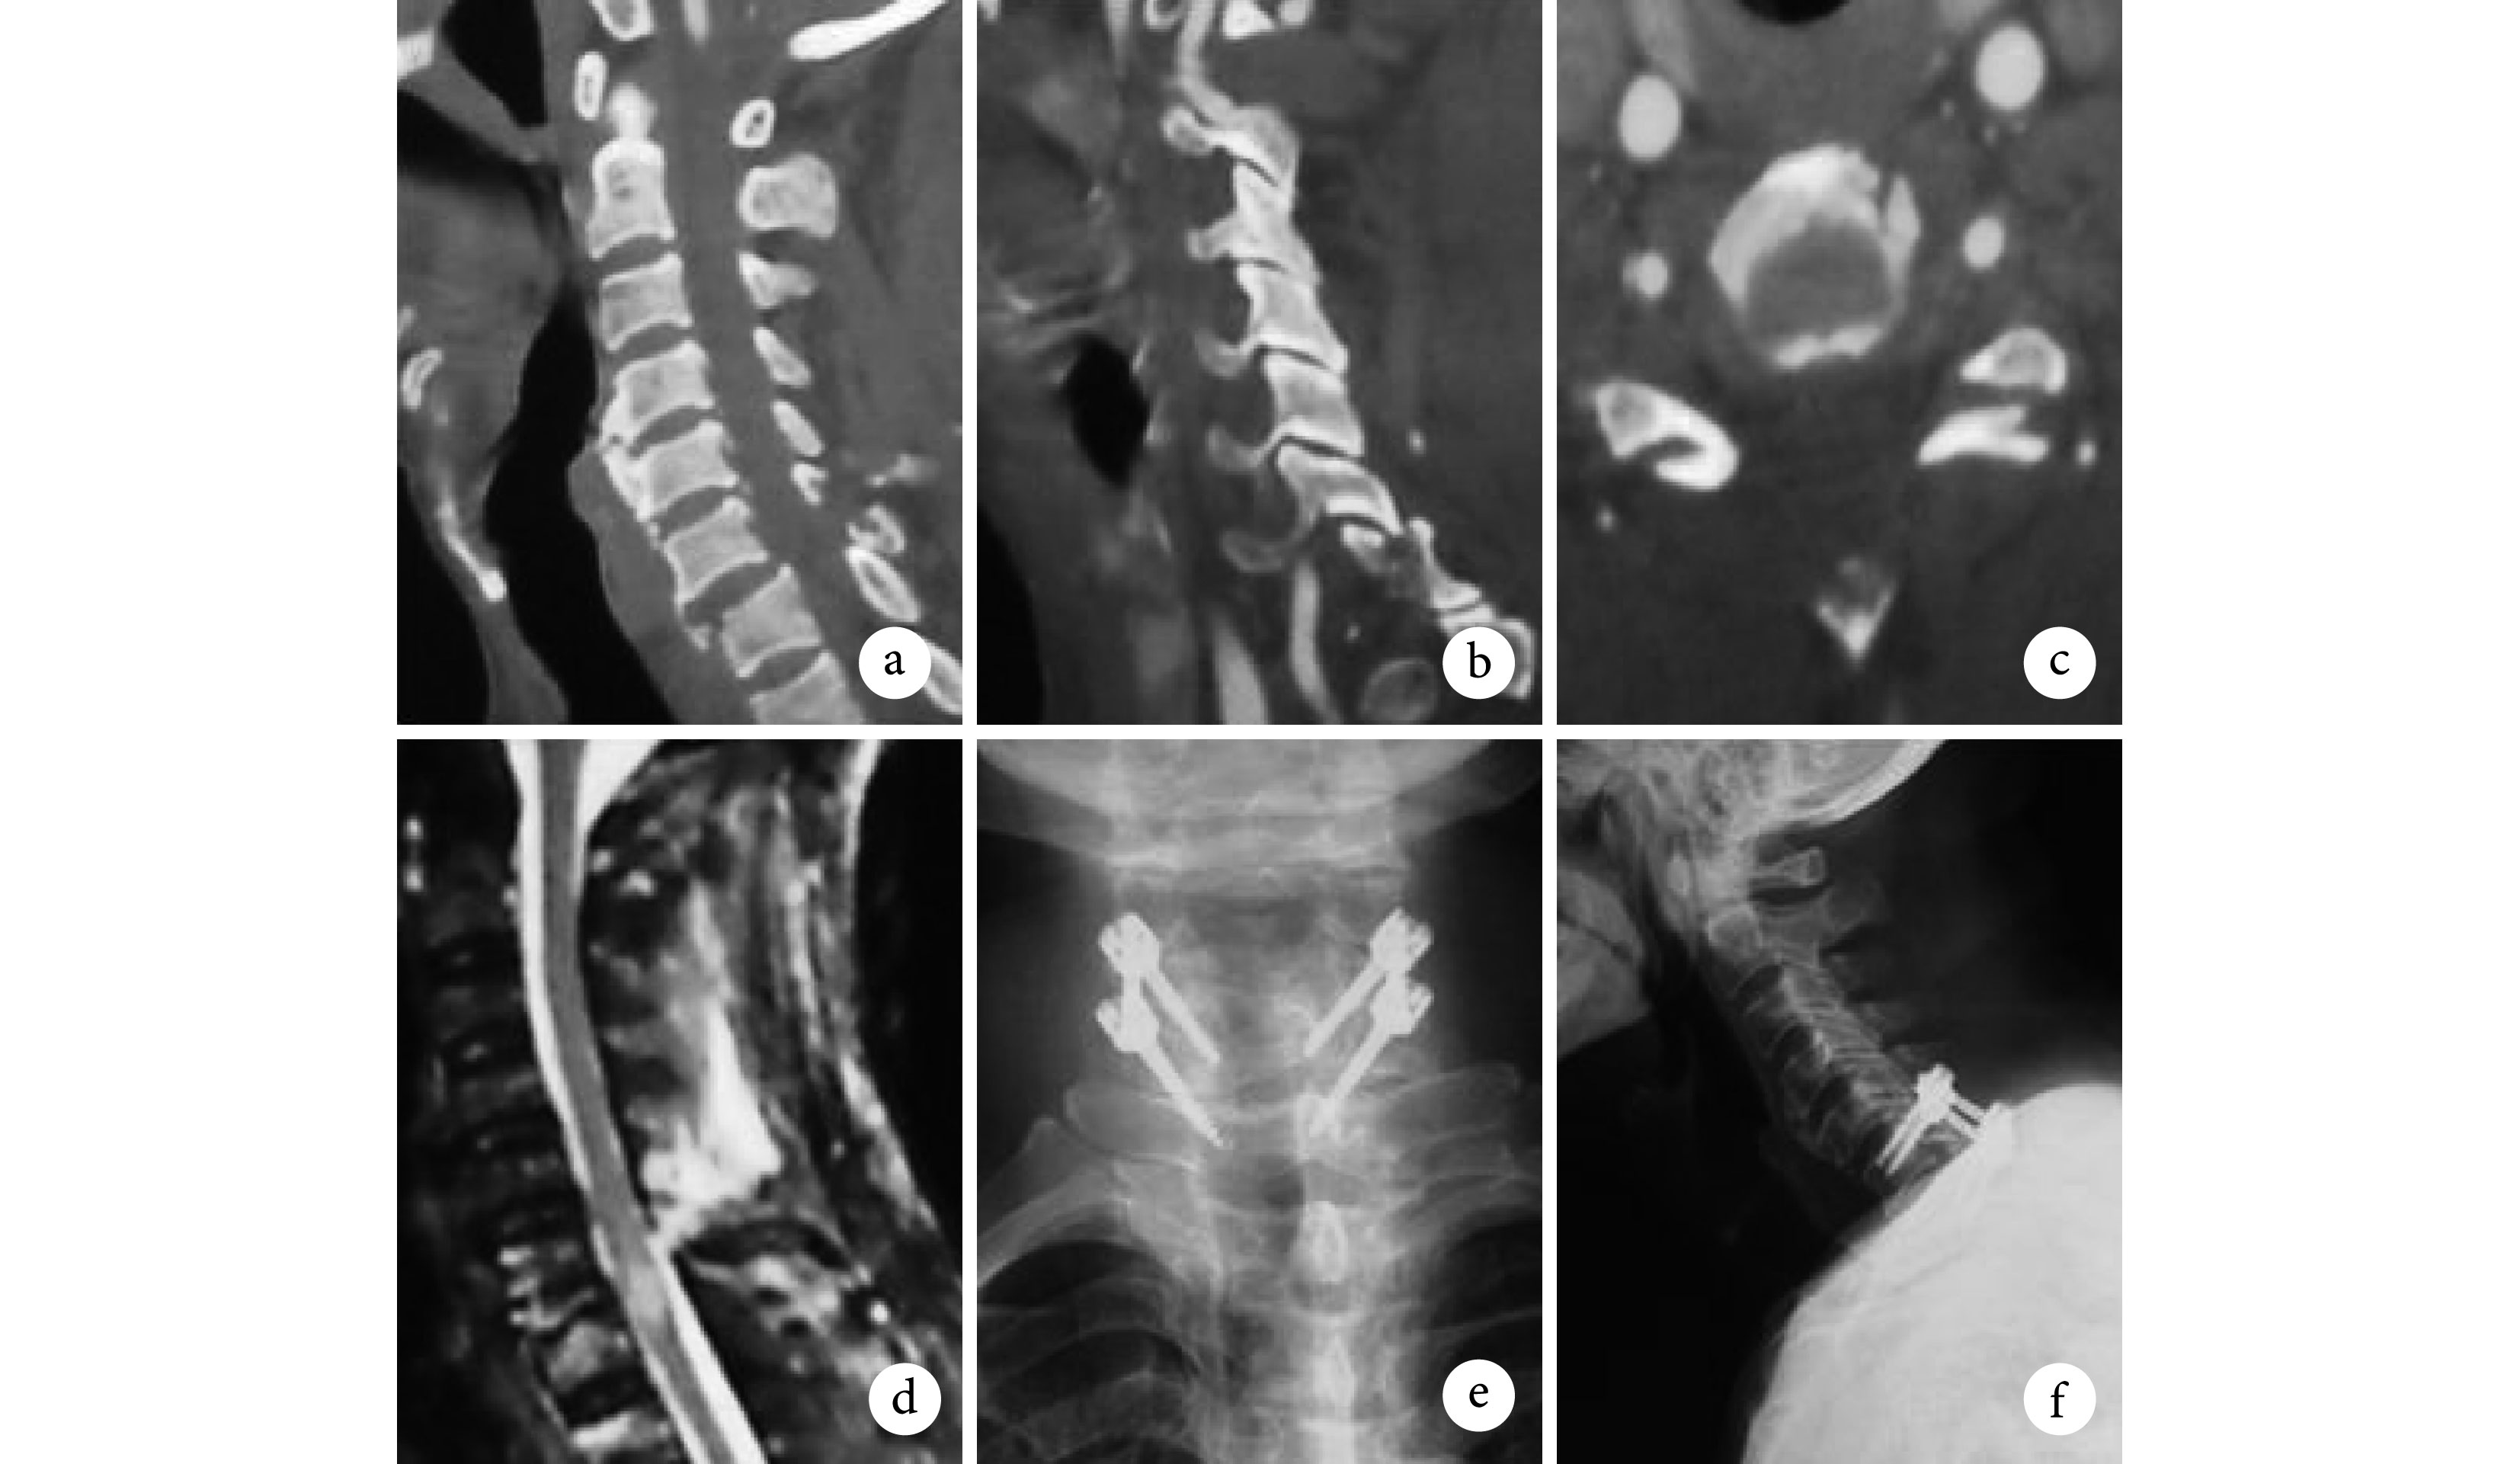

A1 型 35 例,采用頸托保守治療 2 例(1 例骨折愈合,1 例發生遲發性頸椎不穩接受前路 ACDF 手術),前路單節段 ACDF 手術 31 例,ACCF 手術 2 例(2 例患者合并頸椎管狹窄,脊髓損傷,為取得廣泛減壓采取 ACCF)(圖 1);A2 型 7 例,采用后路椎間孔減壓、椎弓根螺釘固定融合 4 例,前路單節段 ACDF+后路椎間孔減壓 2 例,前路單節段 ACDF+后路椎間孔減壓+側塊螺釘固定 1 例(圖 2); B 型 5 例,采用前路單節段 ACDF 手術(圖 3);C 型 21 例,采用前路雙節段 ACDF 手術 14 例,ACCF 手術 6 例,后路椎弓根螺釘固定+單開門椎管擴大成形術 1 例(圖 4)。術后出現 C5 神經根麻痹 1 例,頸椎前方切口血腫 2 例,肺部感染 3 例,無切口感染及神經損害加重病例。62 例(91.2%)患者獲得隨訪,隨訪時間 6~36 個月,平均 14 個月,全部患者獲骨性融合,無內固定失敗、后凸畸形、相鄰節段脫位等。脊髓損傷恢復至 D 級3 例,E 級 6 例;神經根損傷完全恢復 12 例,部分恢復 9 例。

患者男,58 歲,A1 型骨折,Frankel D 級。a. 術前 X 線片顯示 C3 椎體向前移位;b、c. 術前 CT 示 C3 右側下關節突骨折;d. 術前 MRI 顯示 C3 椎體向前移位,相應平面椎管狹窄;e、f. 行 C3-4 椎間盤切除鈦網植骨鋼板內固定術后正側位 X 線片,顯示頸椎序列良好

患者男,63 歲,A2 型骨折,Frankel B 級。a~c. 術前 CT 顯示 C6 椎體向前移位,C7 上關節突骨折,骨折塊進入椎間孔;d. 術前 MRI 顯示 C6-7 平面脊髓高信號,后方韌帶復合體高信號;e、f. 行 C6-7 椎弓根螺釘內固定術后正側位 X 線片,顯示頸椎序列良好